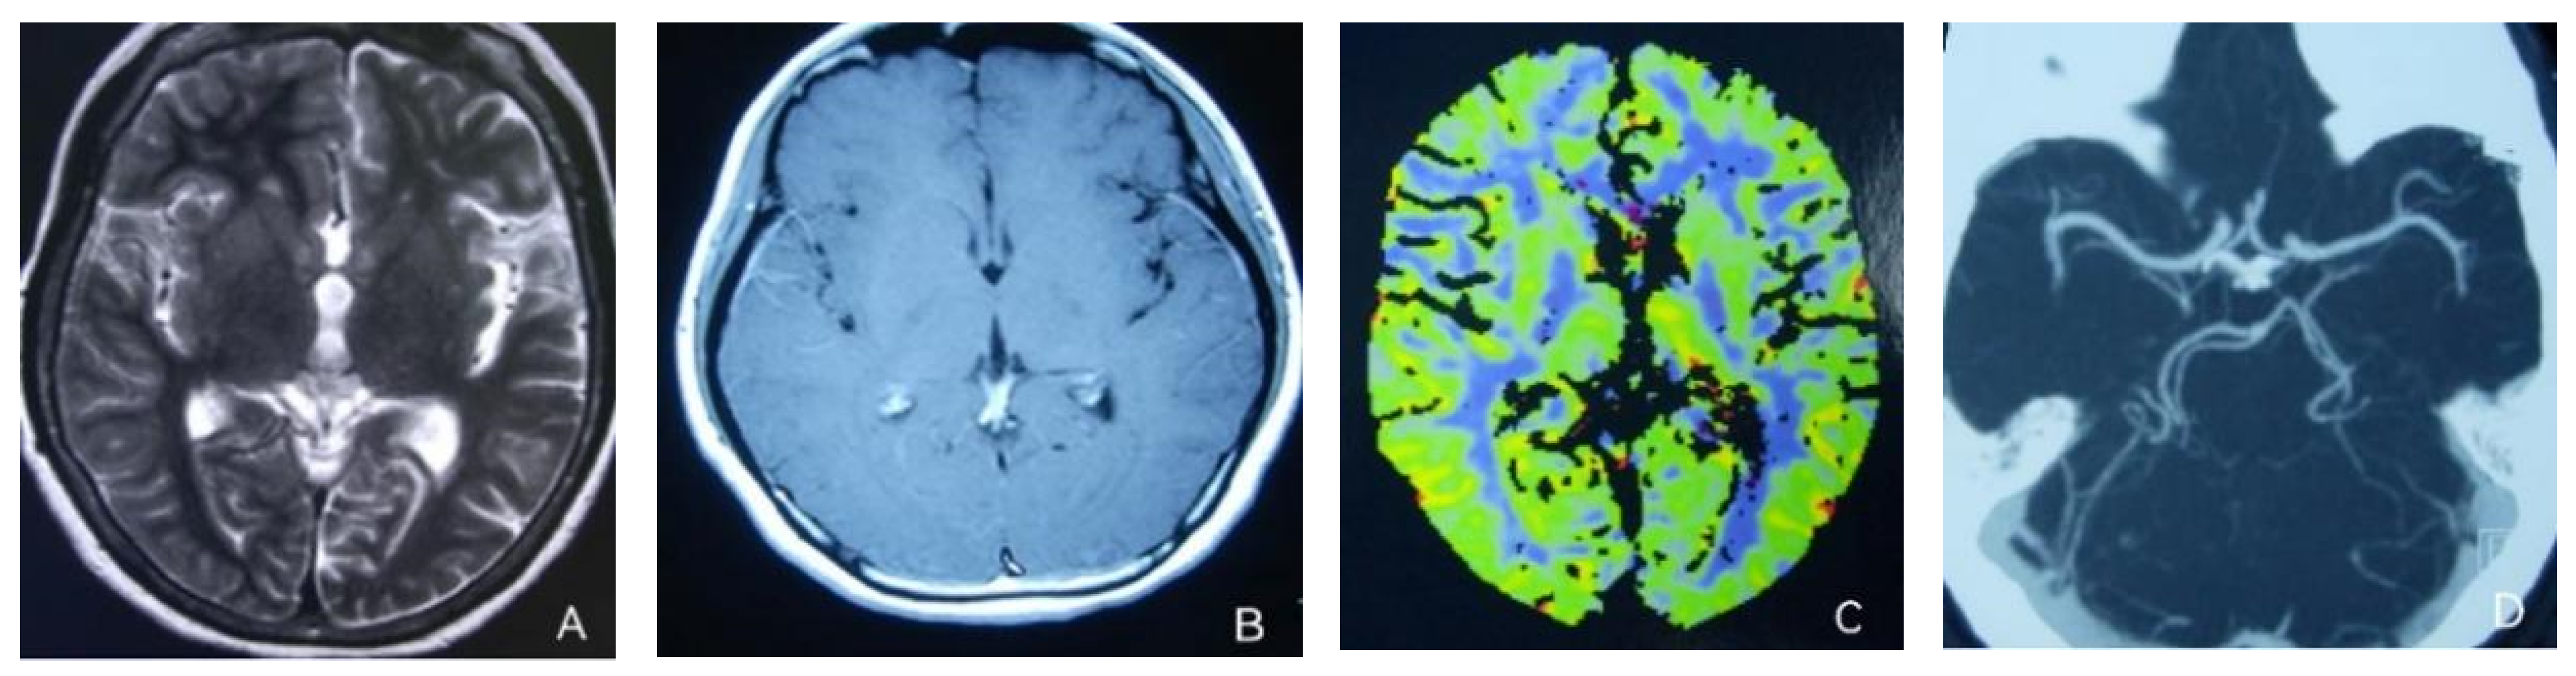

At the age of 51, she had a migraine attack with weakness in the left limb. The headache became increasingly serious, so she was admitted to a hospital six days after the attack. Upon admission, she had severe headaches and left limb weakness, and the neurological examination revealed left hemiparalysis with muscle strength at 3/5 by manual muscles testing (MMT). A brain MRI (magnetic resonance imaging) on day two of admission revealed cortical swelling in the right cerebral hemisphere (Figure 1A), and on the day three of admission, the magnetic resonance angiography (MRA) showed a slight decrease in the branches of the left middle cerebral artery (MCA). The main trunk of the left posterior cerebral artery (PCA) was slender contralateral, and its branches were significantly reduced contralaterally (Figure 1B). Symptoms persisted. On day five of admission, the patient had a focal epileptic seizure, which was followed by two more seizures. Subsequently, the patient’s left limb weakness gradually worsened, the neurologic examination revealed left hemiparalysis with muscle strength at 0/5 by MMT, and she gradually developed unconsciousness to light coma. Brain CT scans during coma revealed swelling of the right cerebral cortex (Figure 1C). Contrast-enhanced brain MRI showed swelling and diffuse enhancements in the cortex of the right cerebral hemisphere (Figure 1D). Perfusion-weighted imaging (PWI) showed right hemisphere hyperfusion (Figure 1E). Based on her medical history and presentation at admission, a lumbar puncture was performed, and the cerebrospinal fluid pressure (CSF) was 204 mm H2O. The biochemical and cytologic examination of the CSF revealed normal chloride, glucose and cell counts and classifications, in addition to normal protein levels. The CSF tested negative for bacteria, viruses, fungi and autoimmune encephalitis. Whole-exome sequencing showed a missense mutation (c.2473G > A, p.Glu825Lys) in exon 18 of ATP1A2. Based on a series of tests, the patient was diagnosed with FHM2 caused by a pathogenic ATP1A2 mutation. During hospitalization, we dehydrated the patient, gave the patient paracetamol for symptomatic treatment and an intramuscular injection of phenobarbital to control seizures. On the 15th day after admission, consciousness and hemiplegia improved, and the headache was relieved; the patient was discharged after 22 days. She was back to normal, and at later follow-up, the patient’s brain MRI (Figure 2A), contrast-enhanced brain MRI (Figure 2B), PWI (Figure 2C) and computed tomography angiography (CTA) all returned to normal (Figure 2D). The time course diagram of the disease in our patient is presented in Figure 3.

Figure 3.

Time course of the disease. Diagram illustrating time course of disease in our patient.